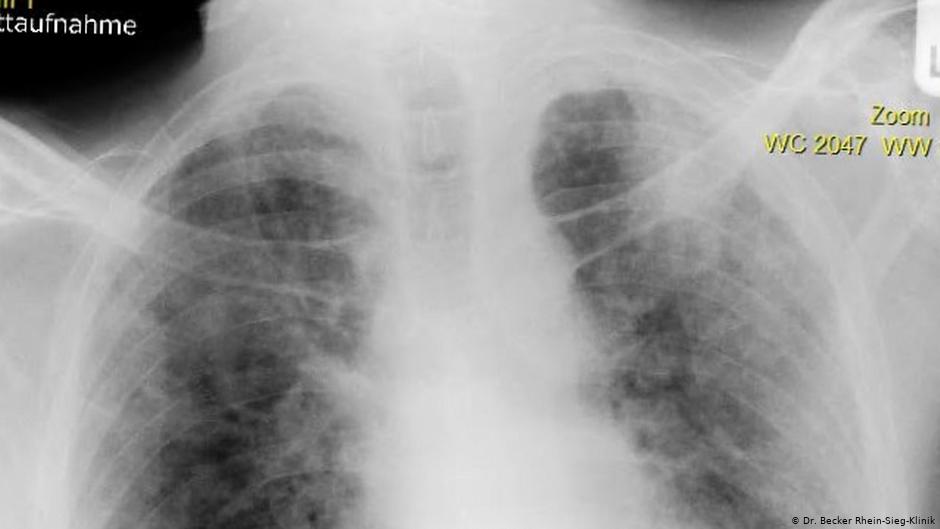

Немец Петер Шмидтген (Peter Schmidtgen) — один из тех, кто перенес COVID-19 в наиболее тяжелой форме. Рентгеновский снимок его легких сейчас показывают друг другу врачи как пример губительного воздействия нового коронавируса SARS-CoV-2 на организм человека.

В состоянии искусственной комы он пролежал два месяца. Все это время он был подключен к аппарату искусственной вентиляции легких. «Его легкие были в ужасном состоянии. Они практически перестали функционировать, потому что не получали кислород», — рассказывает лечащий врач Сильвия Линденберг (Silvia Lindenberg).

По ее словам, врачи из других клиник, куда вынуждены были на время перевезти находящегося в коме Шмидтгена, просто теряли дар речи, когда видели снимки его легких. Они были похожи на один большой рубец.